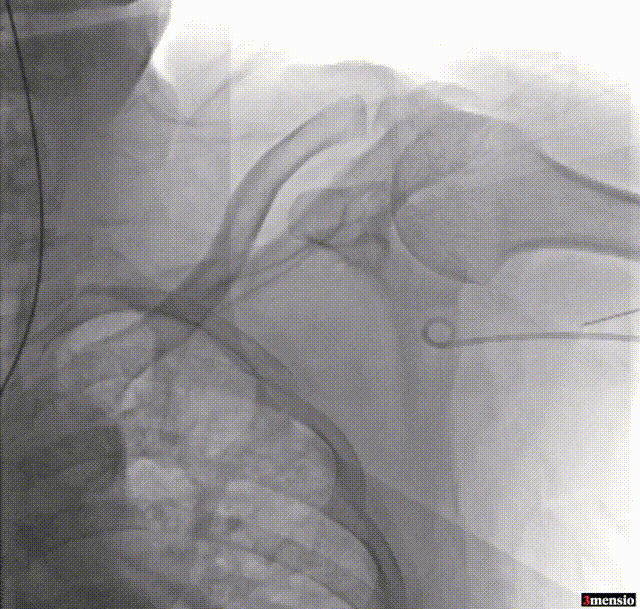

3.猪尾导管置于主动脉根部造影;

主动脉根部造影